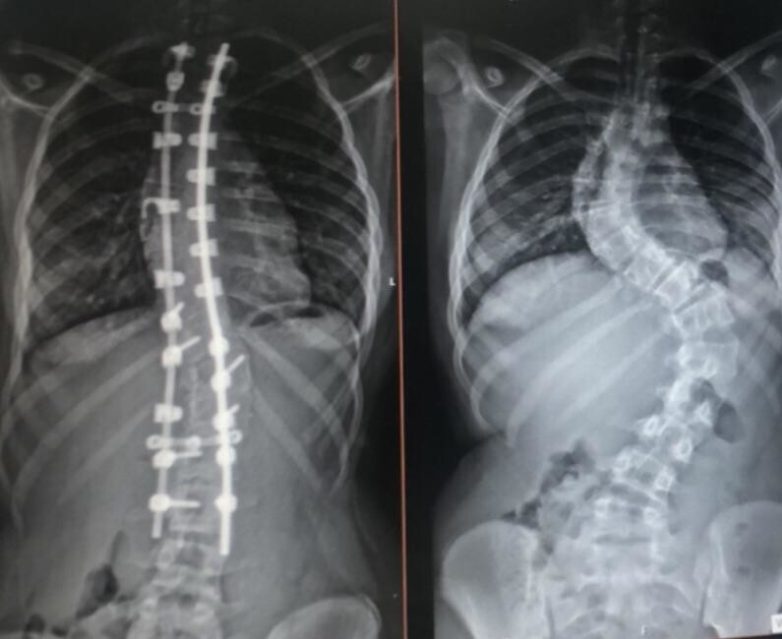

9. Позвоночник до и после операции